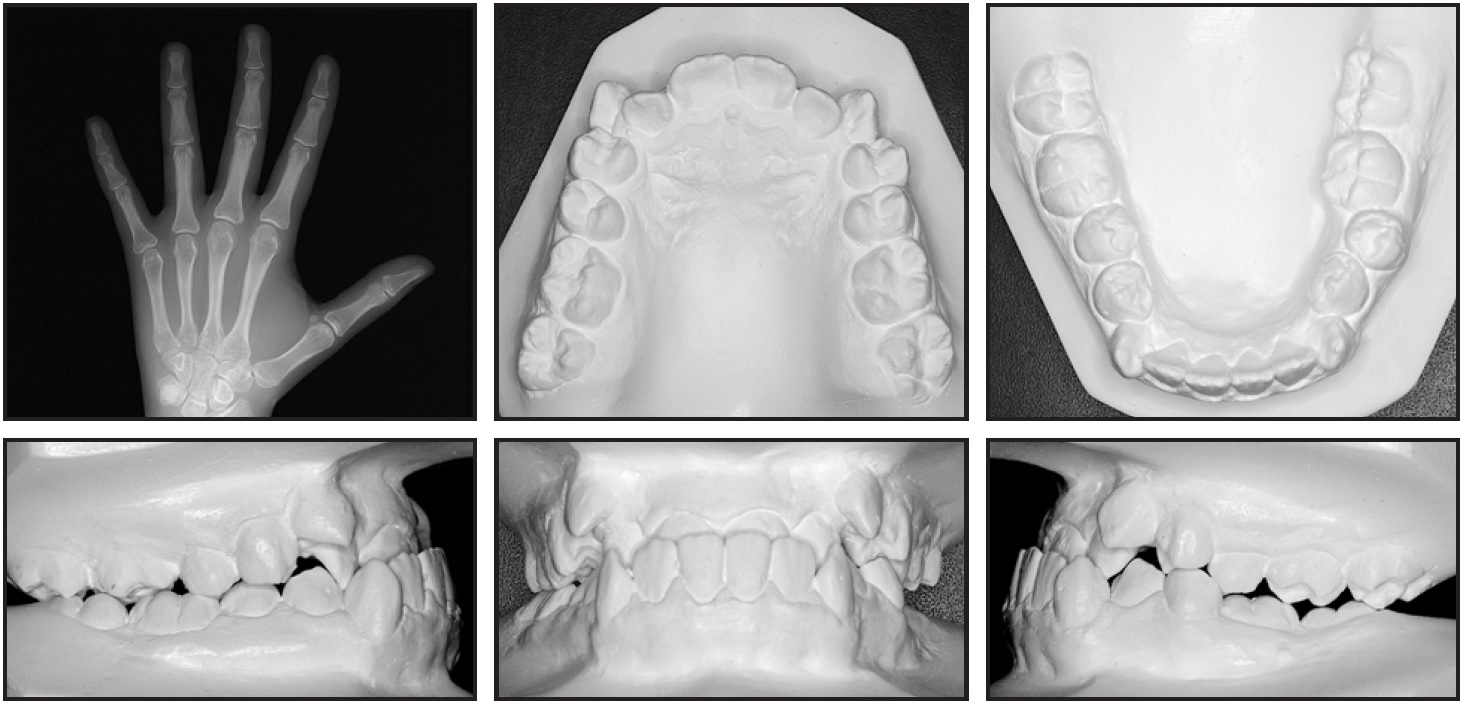

A 15-year-old female with the chief complaints of an anterior crossbite and crowding was referred for orthodontic treatment. The patient had a Class III dental relationship, an anterior crossbite, ectopic canines, and a buccal crossbite on the left side (Fig. 1A).

Fig. 1 15-year-old female patient with Class III dental relationship, anterior crossbite, ectopic canines, buccal crossbite on left side, and concave profile before treatment (continued in next image).

She exhibited a symmetrical face with a dolichofacial tendency and a concave profile with a strong chin projection. Intraoral examination found a negative overjet, a 4mm overbite, and edge-to-edge Class III molar relationships on both sides. The maxillary and mandibular arches displayed severe crowding (–13mm and –10mm, respectively) with a flat curve of Spee. The maxillary dental midline was coincident with the facial midline, but the mandibular dental midline was deviated 1mm to the left (Fig. 1B).

Fig. 1 (cont.) 15-year-old female patient with Class III dental relationship, anterior crossbite, ectopic canines, buccal crossbite on left side, and concave profile before treatment.

The panoramic radiograph showed the presence of all teeth except the upper third molars. A hand-and-wrist x-ray indicated that the patient was in her final stage of growth, with fusion of the epiphysis and metaphysis of the radius almost completed.9 Cephalometric analysis (Table 1) confirmed a skeletal Class III pattern (ANB = .37°, Wits appraisal = 0mm) with protrusive jaws (SNA = 83.94°, SNB = 83.57°) and a hyperdivergent growth pattern (SN-MP = 41.12°). The maxillary incisors were proclined (U1-NA = 25.05°), as were the mandibular incisors (IMPA = 85.71°).